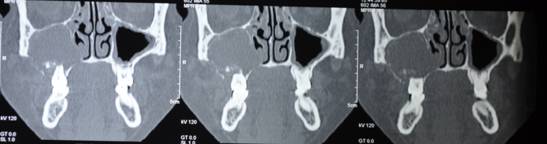

C T SCAN CORONAL SECTION SHOWS THE EXTENT OF DISEASE

C T SCAN AXIAL SECTION SHOWS EXTENT OF DISEASE

C T SCAN CORONAL AND AXIAL SECTION SHOWS EXTENT OF DEFECT AFTER RESECTION